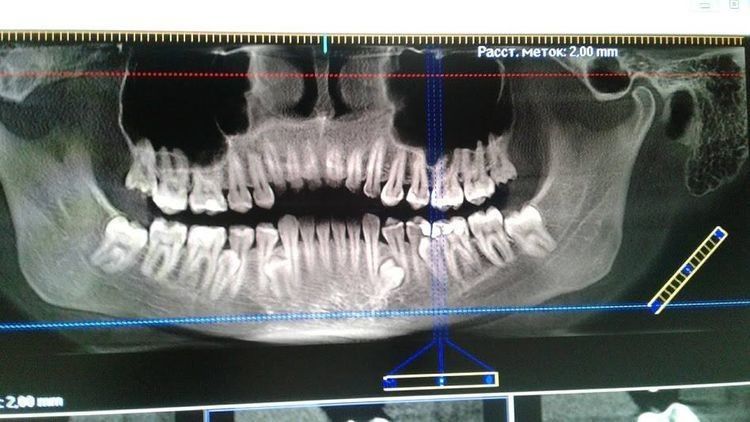

У Юлії Фоміної зі Світловодська замість 32 зубів — 36

Незвичайна жінка-«акула» має 36 постійних зубів, повідомляє на своїй сторінці у «Фейсбуці» керівник Національного реєстру рекордів України Лана Вєтрова.

З них чотири — додаткові корінні, що є рідкісною аномалією.

Зазначимо, що мешканка Світловодська ледве не дотягнула до світового рекорду — 37 зубів.

Фото для Хомів невірних: зубів таки 36.